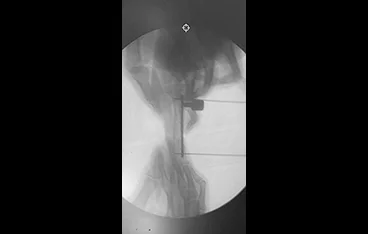

• 복합골절

• 최소침습 골절수술